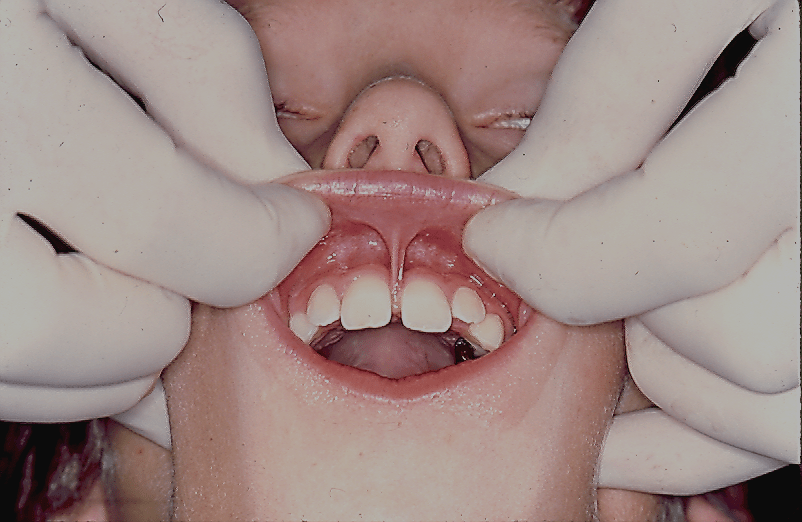

Test for labial frenum surgery

- The upper labial frenum that may need to be removed prior to closing the diastema between the central incisors.